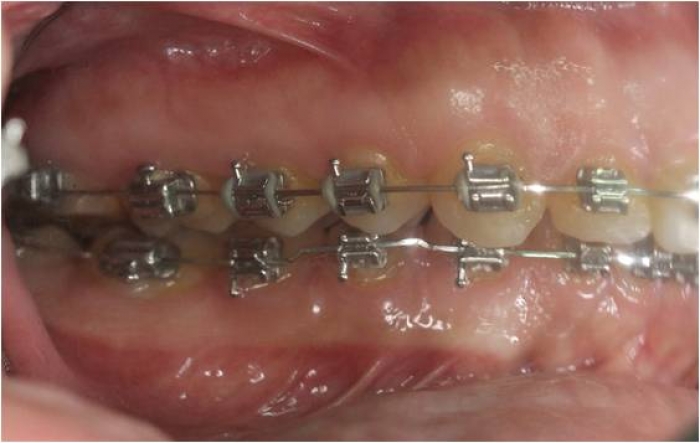

Mordida inicial

Mordida final